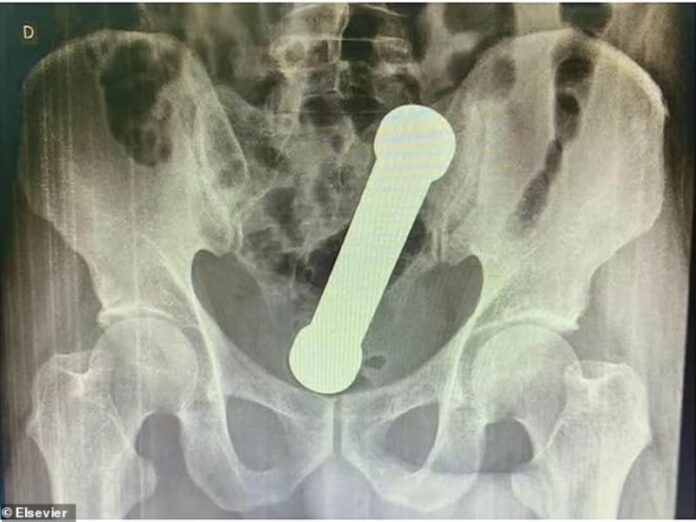

La falta de cooperación del paciente motivó la realización de una radiografía abdominal, la cual confirmó la presencia del objeto alojado entre el colon y el recto.

Los cirujanos intentaron una extracción inicial mediante pinzas quirúrgicas bajo sedación, pero la operación resultó fallida debido al tamaño y la posición del objeto. Finalmente, el equipo médico recurrió a una extracción manual, logrando retirar la mancuerna sin causar daños graves.